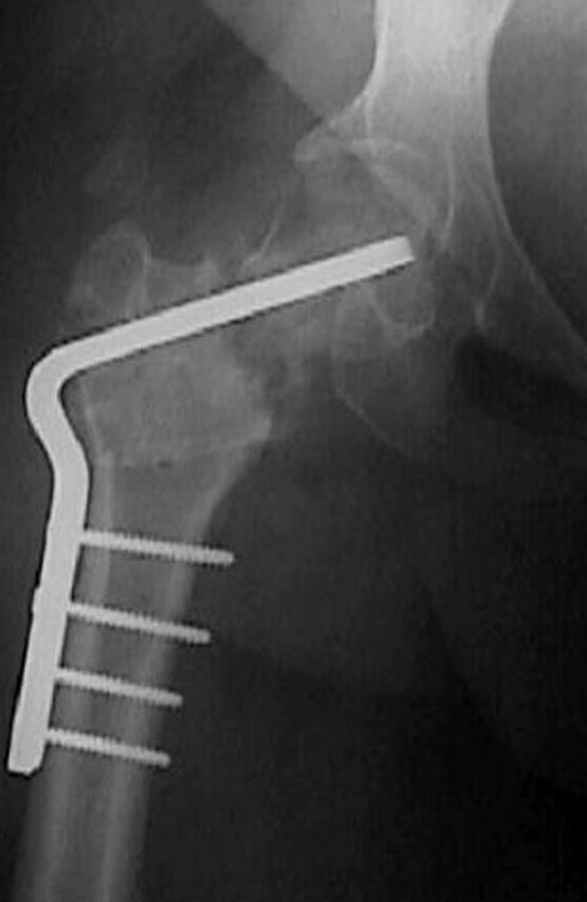

7:30 начало операции, больной на спине, попытка репозиции после анестезии N3, укладка больного на боку, доступ Kocher- Langenbeck, состояние седалищнего нерва около 2.5см кровоподтек, через joistick головка бедра приподнята, освобовождение сустава, фрагмент заднего края более 3х4 см репонирован на свое место. После промывания

сустава, репозиция вывиха (N4), фиксация фрагмента 2.7(4) мм шурупами и допольнительно реконструктивной пластиной на 8 дырок, фиксация 3.5мм шурупами проксимально и дистально.

Интраоперционные N5 косая запирательная и N6 подвздошный снимок

11:50 больной в послеоперационной, рентгенограмма N7, компьютерная томограмма в тот же день N8-10

На рисунке N1 предоперационный план лечения ложного сустава шейки бедра- линия ложного сустава, угол и направление введения импланта, клиновидная остеотомия в градусах и миллиметрах, второй снимок после коррекции, расчет, на сколько удлиняется конечность и размеры импланта;

N3 рисунок окончательный снимок, после операции моя рентгенограмма должен выглядеть примерно как эта картина. На N4 снимке клин перед удалением; N5 послеоперации 3 нед.; N6 окончательная рентгенограмма.

варус при проксимальном отделе 95 градусной пластиной.